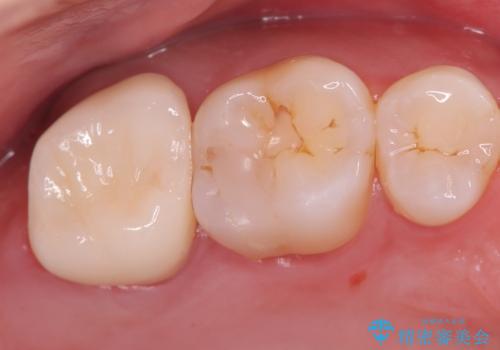

虫歯の治療 オールセラミッククラウン

- 他院にて以前治療した修復物の下に虫歯を認めたため、オールセラミックにて修復治療を行なっております。

オールセラミッククラウンは天然歯と同様に透明感を出すことができ、より審美的な治療が可能です。